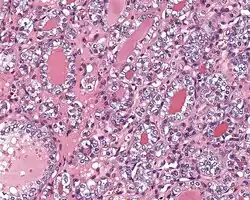

4) Must have the characteristic nuclear features of papillary thyroid carcinoma, although sometimes the features are patchy in distribution without all of the tumor showing those features. The nuclear features can be divided into three main categories:

- Nuclear size and shape: nuclear enlargement, nuclear elongation, and nuclear overlapping and crowding. Loss of nuclear polarity, with nuclei at the lumen, middle, or basal zone of the cells is also a helpful finding.

- Nuclear membrane irregularities: irregular nuclear contours, nuclear grooves and folds, "rat-bites" or demi-lune formations, and the presence of intranuclear cytoplasmic inclusions.

- Nuclear chromatin characteristics: nuclear chromatin clearing, often with condensation or margination along the nuclear membranes, resulting in accentuated nuclear margins, glassy nuclei, or fine, even delicate, powdery nuclear chromatin.